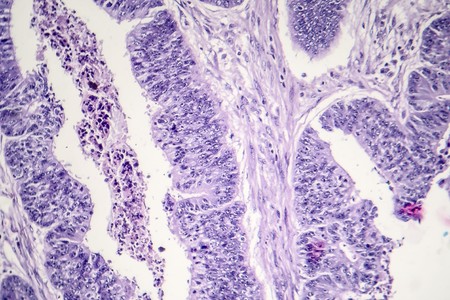

Breast cancer of the woman diseased tissue 100x

Breast cancer, light micrograph, photo under microscope

Hard breast cancer, light micrograph, photo under microscope